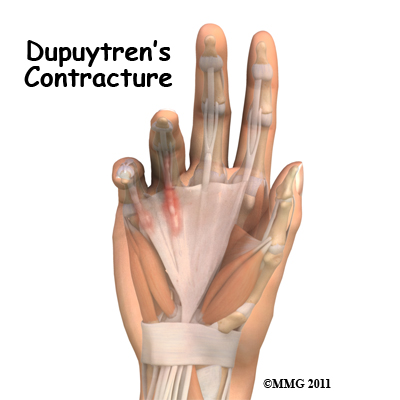

Dupuytrens Contracture Surgery Patient Guide

Dupuytren's contracture is a fairly common disorder of the fingers. It most often affects the ring or little finger, sometimes both, and often in both hands. Although the exact cause is unknown, it occurs most often in middle-aged, white men and is genetic in nature, meaning it runs in families. This condition is seven times more common in men than women. It is more common in men of Scandinavian, Irish, or Eastern European ancestry. Interestingly, the spread of the disease seems to follow the sa...